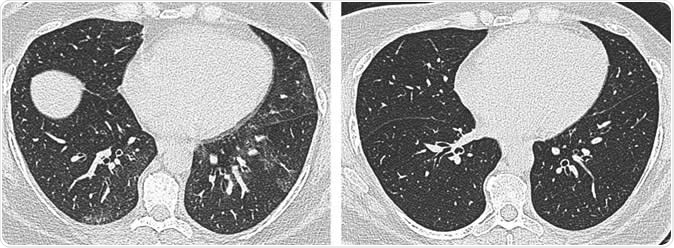

Axial unenhanced inspiratory CT images of the lungs in 51-year-old woman (a) before and (b) 6 months after bariatric surgery with 31-kg weight loss (body mass index decrease, 36.1%). The mosaic attenuation seen before surgery resolved after surgery.  Image Credit: Radiological Society of North America

In the study, all of the participants who had weight loss surgery lost a mean body mass index of about 10.5 kg/m2. To see the respiratory status of these patients, the team used a CT scan to measure the size and shape of the trachea and evaluate for air trapping, also called gas trapping, which is the abnormal retention of air in the lungs caused by the inability to exhale completely. This condition results in a reduction in lung function, and a sign of obstruction in the small airways.

When the team compared CT results before and after the weight loss surgery, they found that the surgery and the resulting weight loss were tied to structural and morphological changes in the lungs and trachea. There was reduced air trapping, which is a strong predictor of improvement in breathing issues or difficulty of breathing, and lower incidence of tracheal collapse.